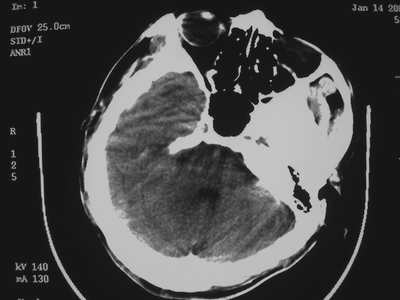

以下是引用卜一在2007-1-19 15:29:00的发言:[br]治疗前:1月14日右侧额叶皮质下低密度影,而治疗后:1月18日右侧阴影消失,新近出现左侧额叶侧脑室前角旁大片状低密度影,边缘模糊。支持—双侧额叶后部缺血性脑梗塞。